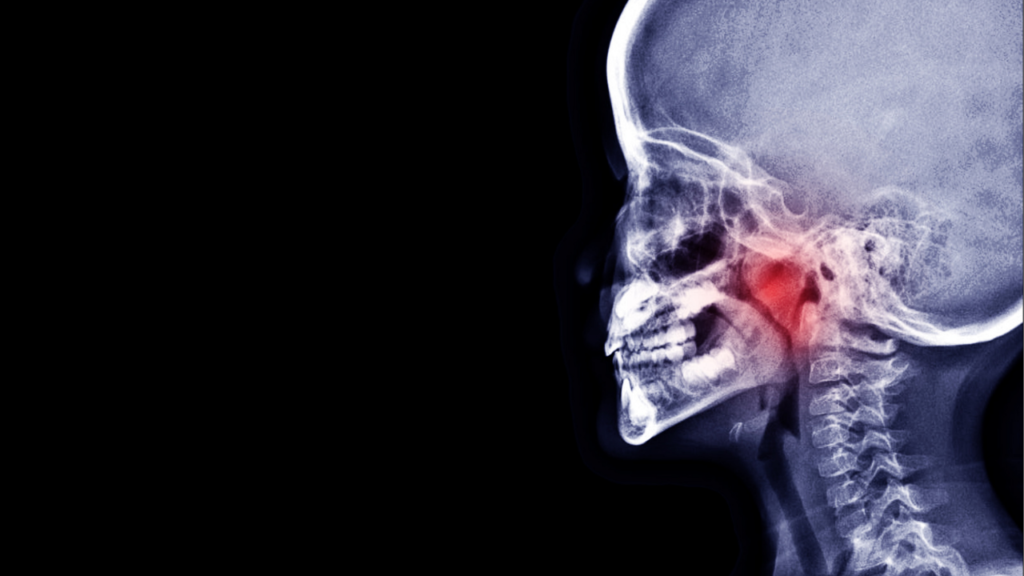

鼻づまりが強く、粘り気のある痰や鼻声を伴うことから、鼻の通りを良くし、炎症を鎮める目的の漢方薬を14日分処方しました。